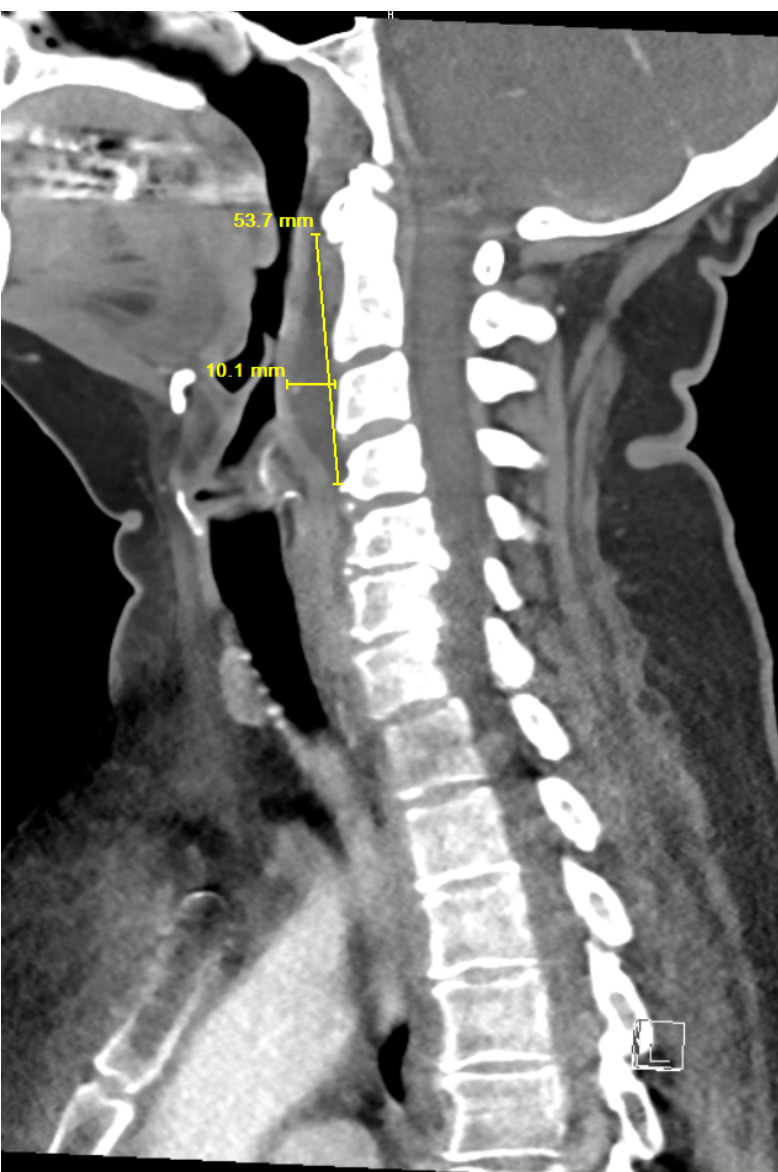

Retropharyngeal abscess (RPA) is an uncommon yet potentially life-threatening condition that is more often seen in young children and may be misdiagnosed in adults presenting with atypical features.1 Retropharyngeal abscess results from spread of antecedent upper respiratory tract infection or traumatic inoculation via foreign body ingestion or medical instrumentation. Clinically, RPA may present with fever, pharyngitis, neck pain, and dysphagia. Diagnosis is often confirmed with imaging studies. We present a case of a 66-year-old female with asthma, hypertension, and gastroesophageal reflux disease (GERD) who presented to the emergency department (ED) for evaluation of neck fullness, shoulder pain, dysphagia, and abdominal pain starting less than 24 hours prior to presentation. Computed tomography (CT) revealed a prevertebral/retropharyngeal fluid collection from the odontoid tip to the C4 vertebral body measuring 5.4 × 1.0 × 3.3 centimeters (cm) in size with associated edema at the left neck base extending into the upper chest, suggestive of retropharyngeal abscess. The patient received intravenous (IV) vancomycin and piperacillin/tazobactam and was transferred to a higher level of care for otolaryngologist evaluation. The patient remained stable without airway compromise while in our department. This case underscores challenges in diagnosing atypical presentations of RPA in adults, emphasizing timely recognition to prevent complications.